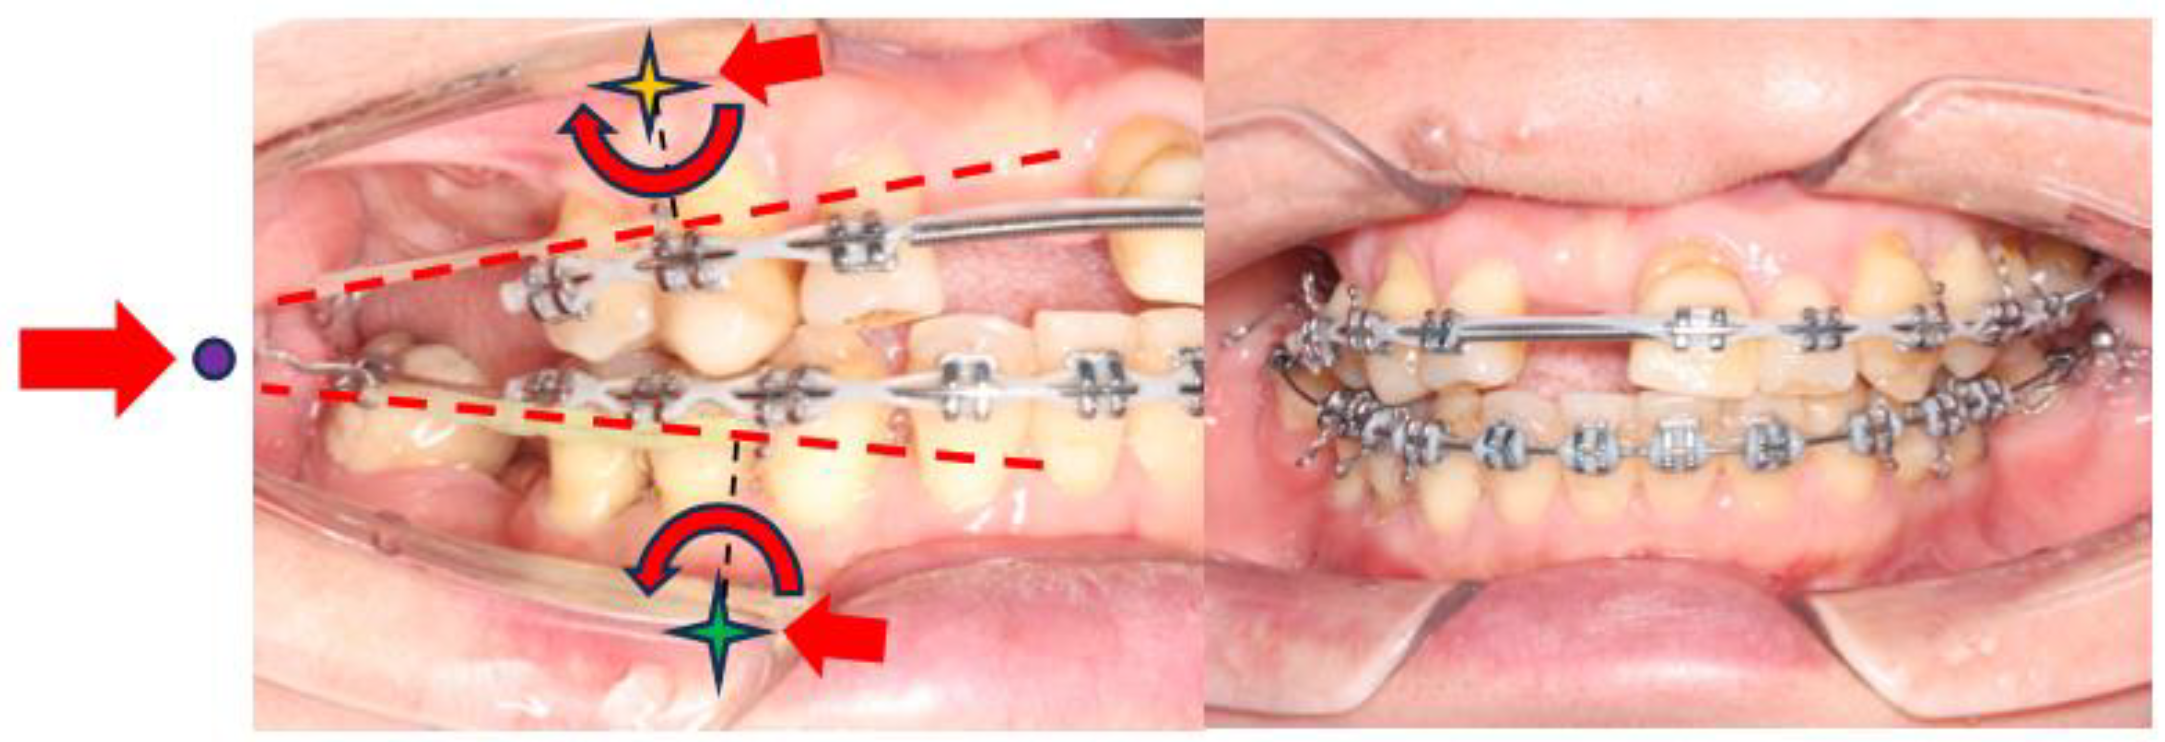

- During the alignment and levelling stage, tooth 35’s crown was displaced distally and rotated disto-bucally, so a box loop capable of delivering the desired magnitude of force and precisely regulating the force direction was used. The box loop increased the total amount of wire between brackets of teeth 34 and 35, which produced a reduced load–deflection ratio and a greater range of action than any other loop type [41]. Furthermore, as the box loop was composed of a series of vertical and horizontal levers contoured to provide a short section of archwire that was freely movable in all planes in which it was activated, we used it to tip the crown of tooth 35 mesially and rotate tooth 35 mesio-lingually [41]. Moreover, sufficient anchorage was provided by the relatively rigid, continuous wire portion adjacent to the box loop, spanning from teeth 34 to 45, which effectively differentiated the active and reactive units.

- (3.4.3)

- As discussed in list 3.3, periodontally compromised teeth would tip excessively in response to orthodontic force which is applied at the regular bracket level. Therefore, if the aim is to achieve bodily retraction of incisors, it is best to bond the brackets as cervically as possible. However, since the pre-treatment upper and lower incisors were proclined, we aimed to achieve ‘uncontrolled tipping’ during retraction, and thus, the brackets were bonded at the regular positions on the upper and lower incisors [42].

- (3.4.4)

- The attempted placement of mini-screws on the upper alveolar bone resulted in dislodgement due to the low sinus floor. This was caused by sinus peumatization which was a continuous physiological process that increased the volume of the paranasal sinuses [43]. To address this, lower buccal shelf mini-screws were used instead to retract the upper arch with Class I elastics.